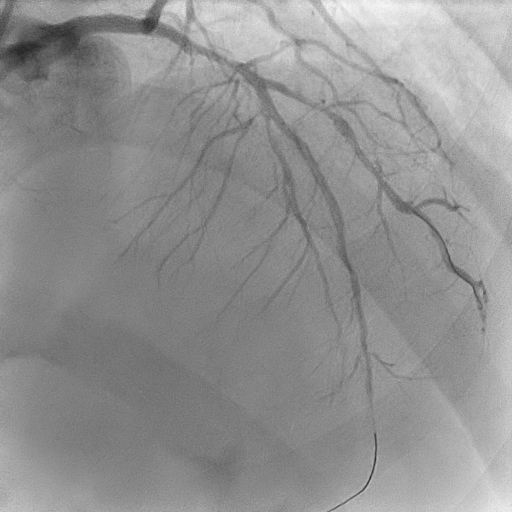

Mid–proximal LAD was sequentially prepared with SC 2.0 balloon and IVUS guidance; distal LAD underwent POBA with SC 1.5 balloon. Lesions in mid LAD and proximal LAD were refined with scoring balloons 2.5/15 and 3.5/15, respectively, treated with DCBs 2.5/30, 2.5/30 and3.5/25. A proximal Type C dissection sealed with a Fantom Encore BRS 3.0/24, post-dilated with NC 3.5/15. LCx and OM prepared with sequential SC balloons 1.5/15 and 2.0/15. Treated with DCBs 2.0/20 at proximal OM and 2.0/30 at LCx. RCA planned for staged angioplasty. Left coronaries were restudied at the time when patient was readmitted for staged angioplasty to RCA, showed excellent results. RCA prepared with POBA to the PL branch with 1.5 SC balloon, scoring balloon 2.5/15 to distal–mid RCA, followed by DCBs 2.75/40 and 3.0/30. A Type A dissection ensued in mid RCA, yet final TIMI III flow achieved.

The Fantom Encore, a third-generation bioresorbable scaffold, exemplifies the principles of coronary rejuvenation by providing transient arterial support before fully resorbing, thereby preserving natural vasomotion and avoiding the long-term liabilities of permanent metallic implants. In this case, it served as an elegant bail-out for a DCB-related dissection, maintaining the philosophy of the ¡°leave nothing behind¡±. Its radiopaque Tyrocore polymer affords fluoroscopic visibility, enhancing procedural precision and ease of usability. The combined use of DCB and BRS delivered an exquisitely refined final angiographic result, underscoring the pursuit of true coronary aesthetics.